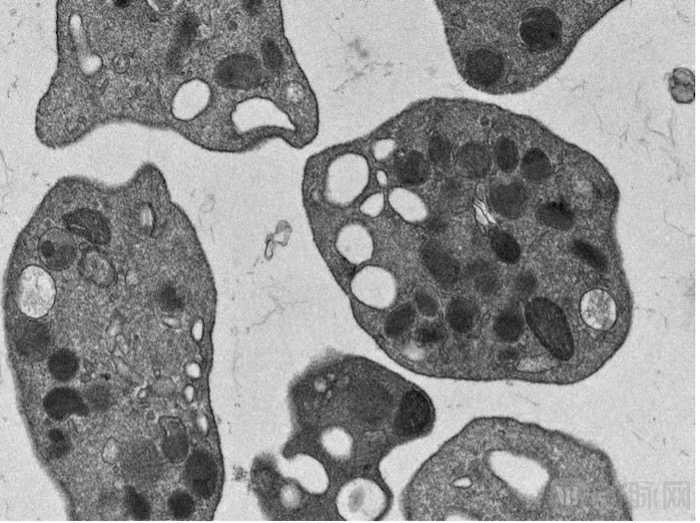

(血小板电镜图,血霁生物提供)

血小板是身体中唯一负责凝血的细胞,它的缺乏会带来全身性的出血,脏器与颅脑出血常伴随不可逆的损伤,乃至危及生命。临床上对它的诉求几乎覆盖医院各科室,也是供应最为紧张、最需要反复输注的成分血。然而全球血小板的供应都靠献血来源,这不仅受到献血率的影响,而且会成为传染疾病的传播媒介。在出现公共卫生事件时,比如新冠疫情期间,血小板的供应更加停摆,造成了很多伤害。朱博士对本媒体表示,她收到了好多问询,表示他们正在寻找血小板,他们真心期待血霁能带来新的曙光。这也让朱博士及团队更加砥砺前行、不懈奋斗。